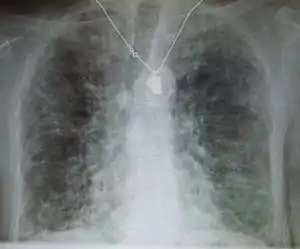

| Other names: Interstitial pulmonary fibrosis | |

| A chest X-ray demonstrating pulmonary fibrosis believed to be due to amiodarone. | |

Pulmonary fibrosis is suggested by a history of progressive shortness of breath (dyspnea) with exertion. Sometimes fine inspiratory crackles can be heard at the lung bases on auscultation. A chest X-ray may or may not be abnormal, but high-resolution CT will frequently demonstrate abnormalities.[3]